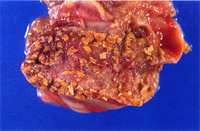

4. 肝:多發局部壞死灶,高倍下可見嗜酸性核內包涵體(圖3,4)。